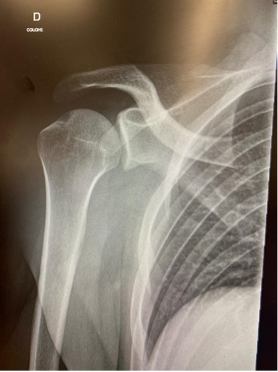

Ces radiographies mettent en évidence une luxation antérieure de l’épaule avant et après réduction.Lors d’une luxation de l’épaule plusieurs étapes sont nécessaire :

1. Effectuer une radiographie afin de confirmer le diagnostic et de vérifier l’absence de fracture sous-jacente.